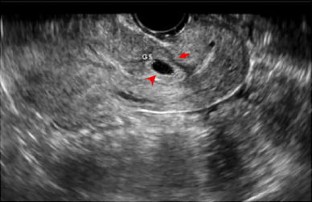

Fig. 2